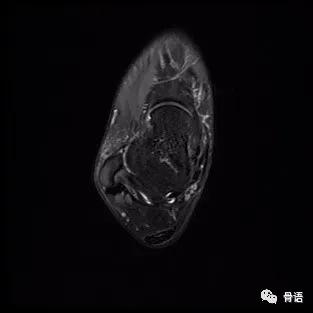

图3 患者术后3个月MR轴位片

图1、图2示术前ATFL连续性中断、显影模糊,提示ATFL撕裂,距骨软骨损伤,骨髓水肿。图3、图4示ATFL关节镜下带线锚钉固定联合PRP治疗术后6个月ATFL完整性存在,张力好,骨髓水肿信号较前减轻。该患者术后随访效果满意,症状较前明显减轻。